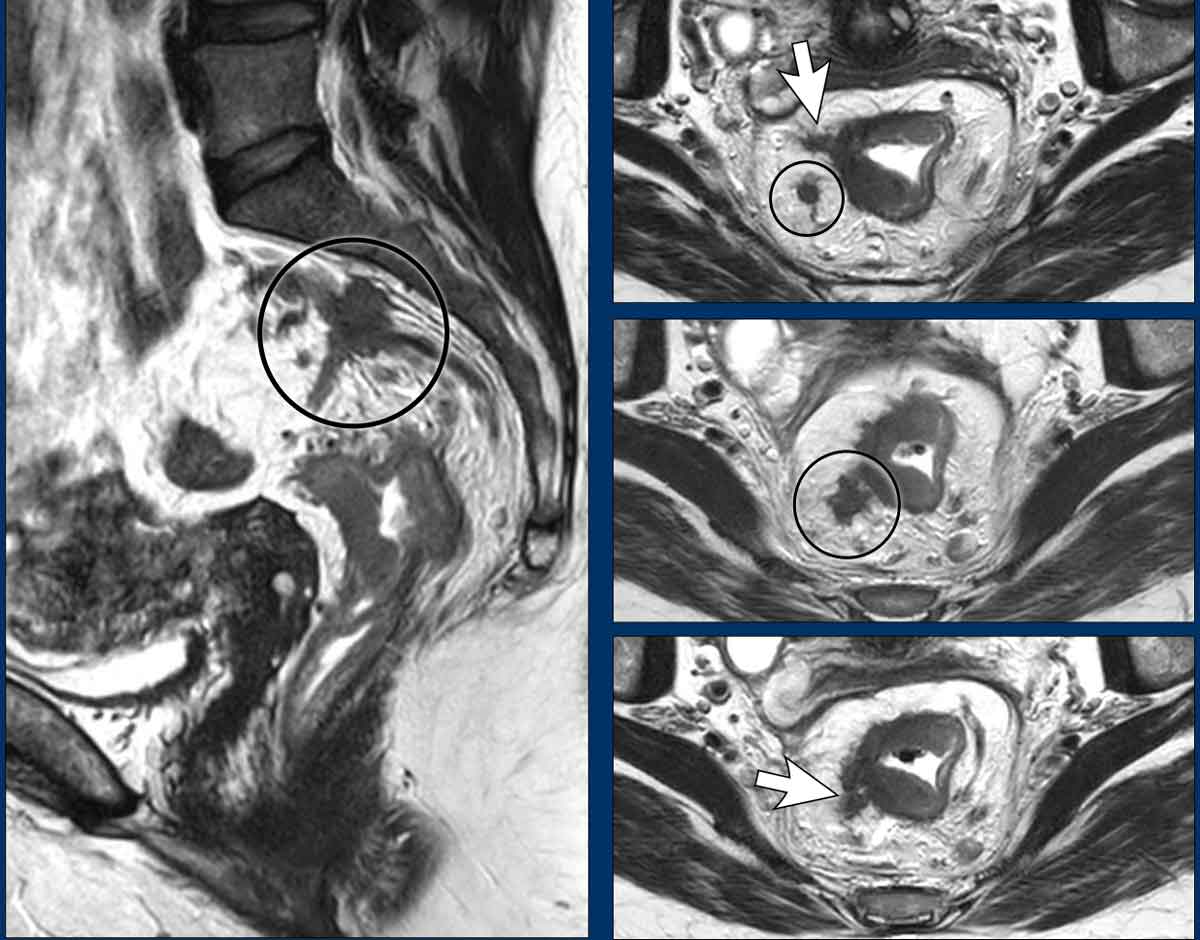

Signet-Ring Cell Rectal Adenocarcinoma

Epidemiology & Prognosis

A rare mucinous subtype (±1%), signet-ring cell carcinoma is associated with high rates of nodal/distant metastasis and poor overall survival.

MRI Features

• Often challenging to identify

• Typically presents as long-segment, diffuse bowel wall thickening

• Submucosal growth pattern, yielding a "target" appearance on axial images

• Diffuse mesorectal fat infiltration is common

Images

The provided images demonstrate a signet-ring cell carcinoma with diffuse rectal wall thickening, the classic target appearance, and mesorectal fat infiltration.